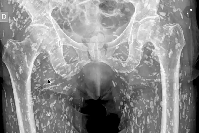

Изучение проблемы низкого качества рентгенограмм на Вашем оборудовании.

В случае перелома шейки бедра компания МосРентген Центр госпитализирует в Склиф для эндопротезирования.